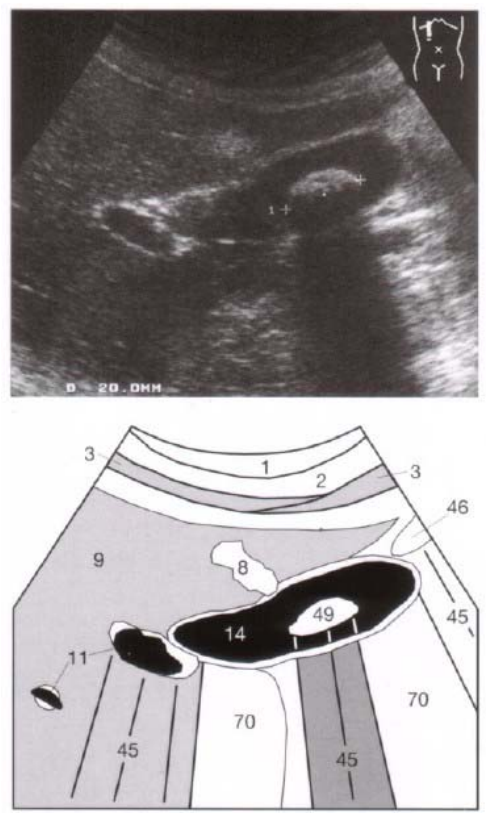

67.下圖為肝臟超音波影像,編號49號所指為何?

(A)膽結石 (B)部分體積假影 (C)肝腫瘤 (D)膽瘜肉